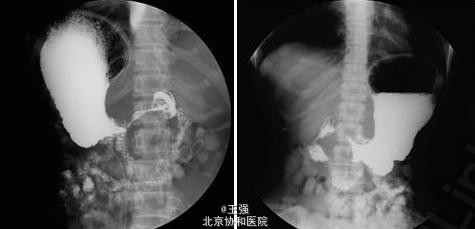

行上消化道造影:胃体大弯侧及胃窦部见巨大充盈缺损,边缘不整,表面凹凸不平,胃壁僵硬,黏膜皱襞中断。胃镜检查:胃底粘膜光滑,蠕动可;胃体皱襞明显增粗、僵硬,无蠕动,粘膜水肿、充血,未见明确溃疡及糜烂,多灶深挖活检8块,质韧;胃体胃腔狭窄,内镜通过有阻力,胃角切迹不能显示,胃窦腔狭小,幽门圆,持续开放。活检病理:(胃体)低分化腺癌。